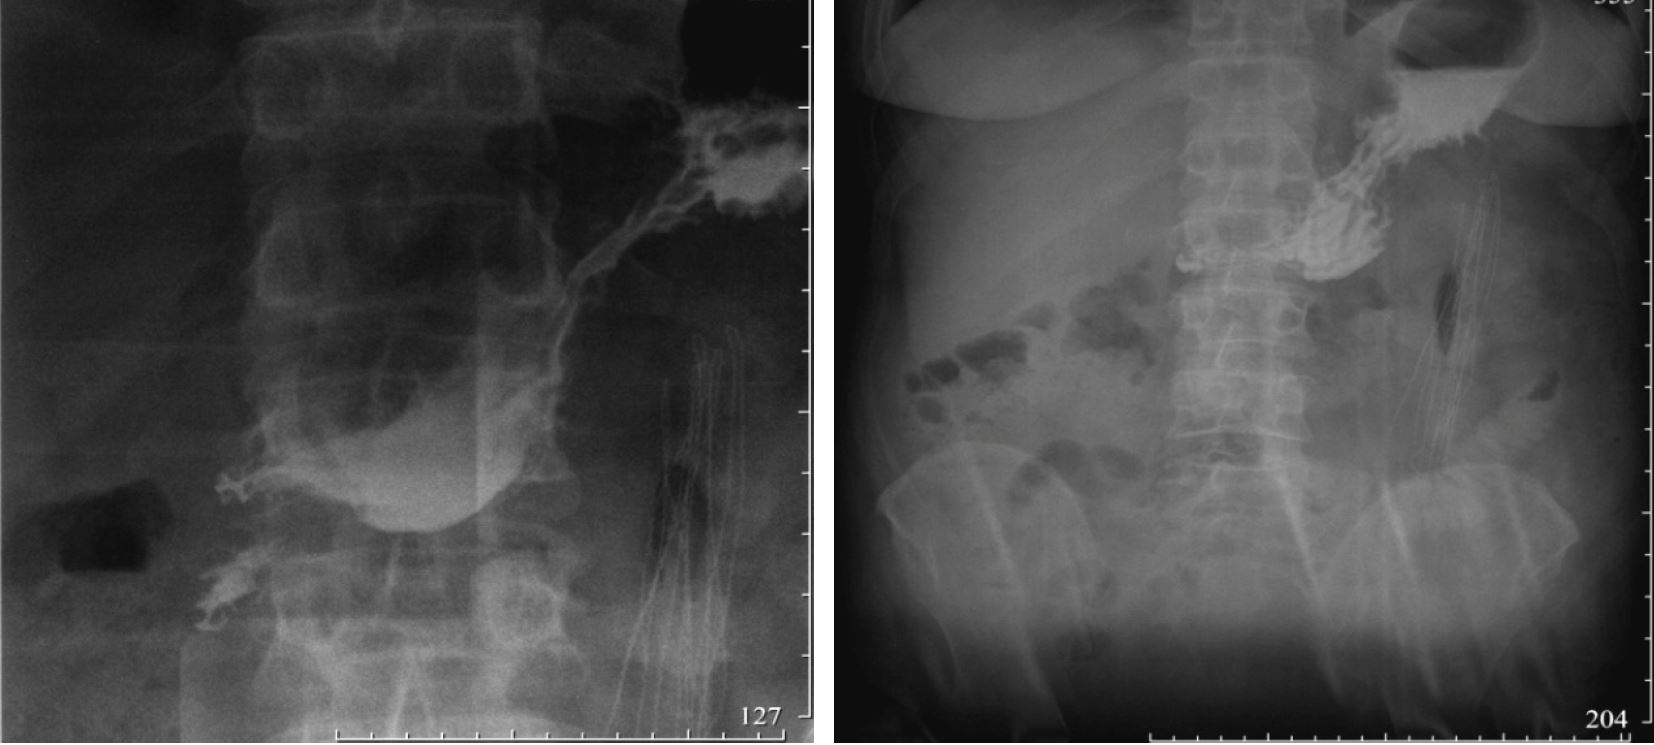

On the 57th day after surgery, the gastric fistula closed. According to the results of X-ray examination of the stomach with a water-soluble contrast agent, no extra contours of the contrast substance were detected. The contrast entered the duodenum in small portions (Fig. 4).

Fig. 4. X-ray of the stomach and duodenum with a water-soluble contrast agent

By the 63rd day after the operation, the pain syndrome was stopped. The pancreatic fistula closed during conservative treatment. There was no negative trend in laboratory or instrumental parameters.